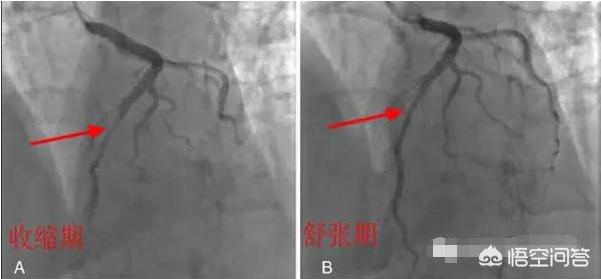

Ce type est plus malchanceux.Dans des circonstances normales, les artères coronaires se trouvent à la surface du myocarde, sous l'épicarde, mais chez les personnes souffrant de "ponts myocardiques", une partie des artères coronaires est enfouie sous le myocarde, et le myocarde qui recouvre le sommet des artères coronaires est connu sous le nom de "ponts myocardiques". Selon le degré de compression du pont myocardique sur l'artère coronaire, on considère généralement que la compression est légère et asymptomatique sur l'ECG au repos, tandis qu'une compression de plus de 40 % entraîne des symptômes cliniques tels qu'une oppression et une douleur thoraciques, une angine de poitrine, etc.La figure ci-dessous illustre la compression d'une artère coronaire par un pont myocardique au cours d'un cycle cardiaque, le segment entier du vaisseau s'amincissant sous l'effet de la compression.

De plus, les artères coronaires comprimées sont plus sujettes au spasme de l'artère coronaire en raison de la pression et de la torsion répétées auxquelles elles sont soumises. Et en raison de la présence de perturbations du flux sanguin telles que des turbulences dans le segment proximal du vaisseau (le sang ne circule pas assez facilement dans le vaisseau), il est plus probable que l'athérosclérose coronarienne (blocage) se produise et, en plus, que la rupture de la plaque, l'hémorragie, la thrombose et le spasme se produisent, entraînant ainsi le développement de syndromes coronariens aigus.Cette situation est vraiment malchanceuse, la suggestion est toujours le même vieux dicton, la quantité d'exercice, l'examen régulier. Car pour l'instant, je n'ai pas entendu parler d'une méthode particulièrement efficace. Mais cette situation peut être évitée, à condition que davantage de personnes comprennent qu'elles sont atteintes de cette anomalie congénitale.